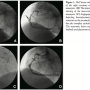

Patient #1. A 71-year-old, male hypertensive with a prior history of triple bypass surgery [left internal mammary to left anterior descending artery (LAD), and saphenous vein grafts (SVG) to circumflex (LCX) and right coronary artery (RCA)] was referred to our department due to angina and clinically positive exercise stress test, with ischemia in the inferior wall in the thallium stress test. The patient underwent coronary angiography, which showed total occlusion of the LAD and circumflex and severe stenosis at the proximal part of the RCA with post-stenotic aneurysm and TIMI-I flow distally (Figure 1A); LIMA and SVG at the LAD and LCX, respectively, were patent and well functioning, while the SVG to the RCA was totally occluded. An ad-hoc percutaneous coronary intervention (PCI) at the RCA was performed. An AL1 guide catheter was used in order to cannulate the artery and after placement of one BMW middleweight and one BMW heavyweight 0.014˝ wire at the distal end of the artery (“buddy” wire technique) and predilation with a 3.0 x 15 mm Maverick balloon (Boston Scientific Corporation, Natick, Massachusetts) at 14–18 atm and a 3.0 x 15 mm Quantum Maverick balloon at 16–26 atm, an attempt was made to advance a 3.0 x 19 mm PTFE-covered Jostent (Abbott Vascular, Abbott Park, Illinois). However, the stent could not be advanced due to lesion severity and pre-stenotic tortuousity. The lesion was then treated with placement of a 3.0 x 18 mm Driver stent (Medtronic, Minneapolis, Minnesota) at 16 atm, which was carefully anchored distally to the aneurysm. The final angiographic result was excellent with no residual stenosis, and normal flow (TIMI-3), while stagnation of the dye at the site of the aneurysm was observed (Figure 1B). A scheduled angiographic follow-up was performed at 4 months, and showed hemodynamically significant in-stent restenosis at the proximal part of the implanted stent, but also complete exclusion of the artery (Figure 1C). The restenotic lesion was treated with predilatation, implantation of a 3.5 x 23 mm Cypher stent (Cordis Corporation, Warren, New Jersey) at 14 atm and post-dilatation with a 3.5 x 8 mm Quantum Maverick balloon at 16–26 atm (Figure 1D). At 2-year follow-up, the patient was asymptomatic with no ischemia at the myocardial scintigraphy.